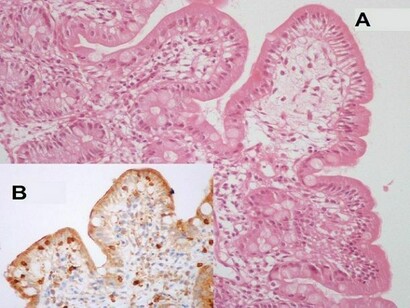

- La gliadina arriva nell'intestino e scatena una reazione "anomala" di alcune componenti del sistema immunitario (di difesa naturale). Alcune strutture del sistema specifico preposto al riconoscimento del proprio corpo (l'HLA, che provoca, per esempio, il rigetto di un organo trapiantato), individuano come "tossica" la gliadina e attivano la produzione di anticorpi e globuli bianchi verso questa sostanza ma anche contro il tessuto intestinale. Questo danno impedisce all'intestino di assorbire i nutrienti dei cibi. La prolungata ingestione di gliadina, inoltre, favorisce la comparsa di altri disturbi seri, come il diabete e la carenza di calcio e di ferro.